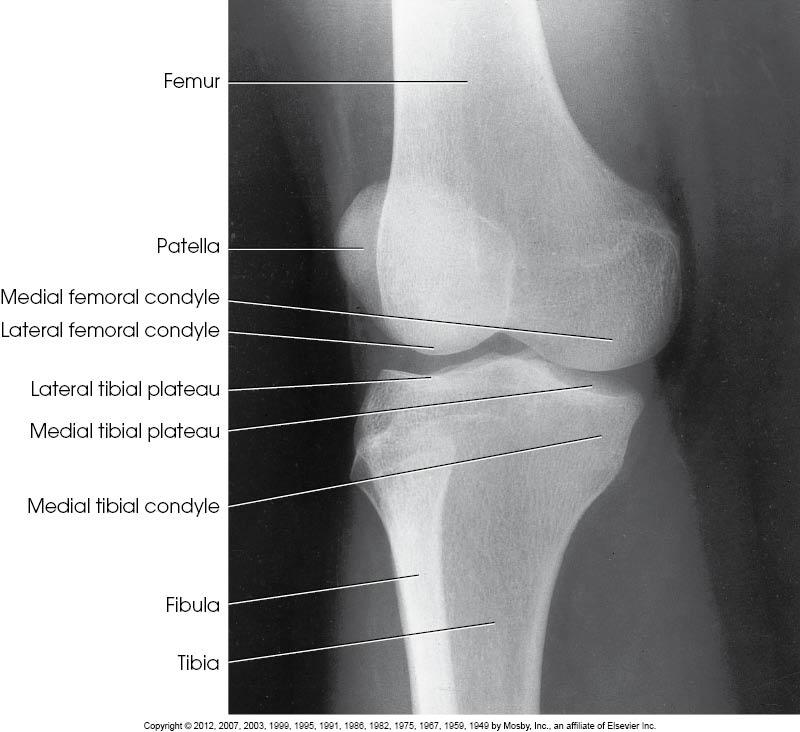

Structures Shown

• Patella projected slightly over the

border of the lateral femoral condyle

• Open knee joint

•

Tibial plateau

• Soft tissue

AP Oblique of the knee, Lateral rotation